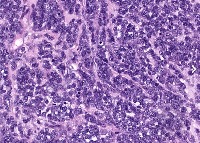

This is an AI laboratory project by Linette Dannah Cartagena, a second year medical student. Ovarian cancer can be classified into four main types: epithelial tumors, germ cell tumors, stromal tumors, and small cell carcinoma of the ovary. This model aims to recognize each type through AI. All one has to do is to simply by upload a photo of the histological slide.